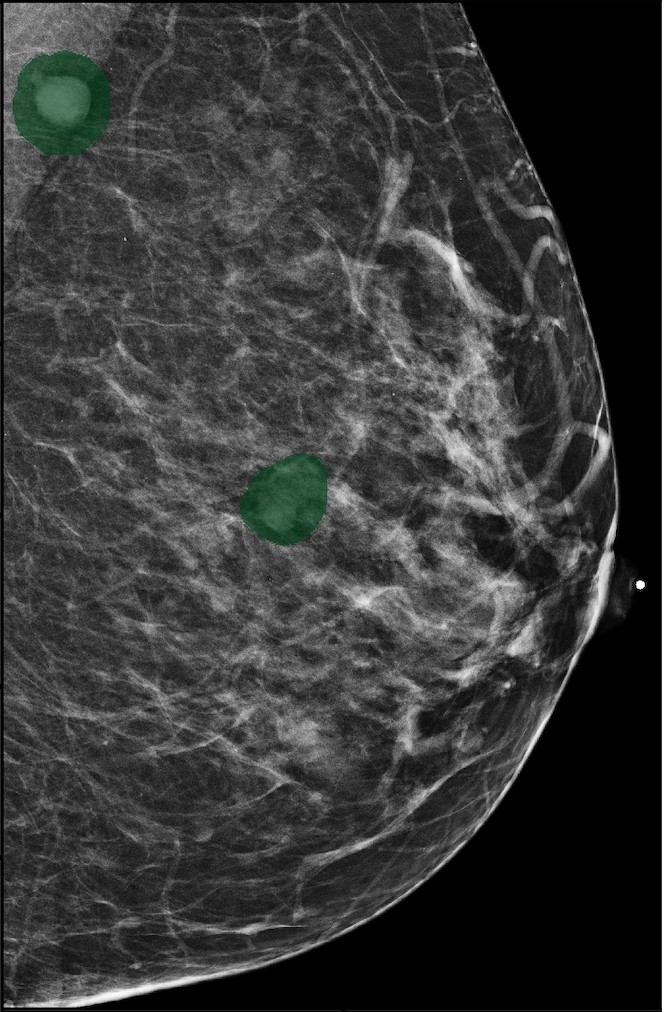

In Figure 7, we visualize saliency maps for four samples selected from the test set. In the first two examples, the saliency maps are highly activated on the annotated lesions, suggesting that our model is able to detect suspicious lesions without pixel-level supervision. Moreover, the attention is highly concentrated on ROI patches that overlap with the annotated lesions. In the third example, the saliency map for benign findings identifies three abnormalities. Although only the top abnormality was escalated for biopsy and hence annotated by radiologists, the radiologist’s report confirms that the two non-biopsied findings have a high probability of benignity and a low probability of malignancy. In the fourth example, we illustrate a case when there is some level of disagreement between our model and the annotation in the dataset. The malignancy saliency map only highlights part of a large malignant lesion with segmental coarse heterogeneous calcifications. This behavior is related to the design of : a fixed pooling threshold cannot be optimal for all sizes of ROI. The impact of is further studied in 3.6. This example also illustrates that while human experts are asked to annotate the entire lesion, CNNs tend to emphasize only the most informative regions. While no benign lesion is present, the benign saliency map still highlights regions similar to that in the malignancy saliency map, but with a lower probability than the malignancy saliency map. In fact, calcifications with this morphology and distribution can also result from benign pathophysiology [42].